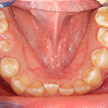

13. 術後下顎

前歯部の叢生および左下2,3番間の乱杭が改善され、全ての歯牙の唇面の連続性が確保されています。当然、口腔清掃しやすい環境になりますし、発音などにも良い影響を与えます。またこれから年齢を重ねても、虫歯や歯周病の予防に繋がります。